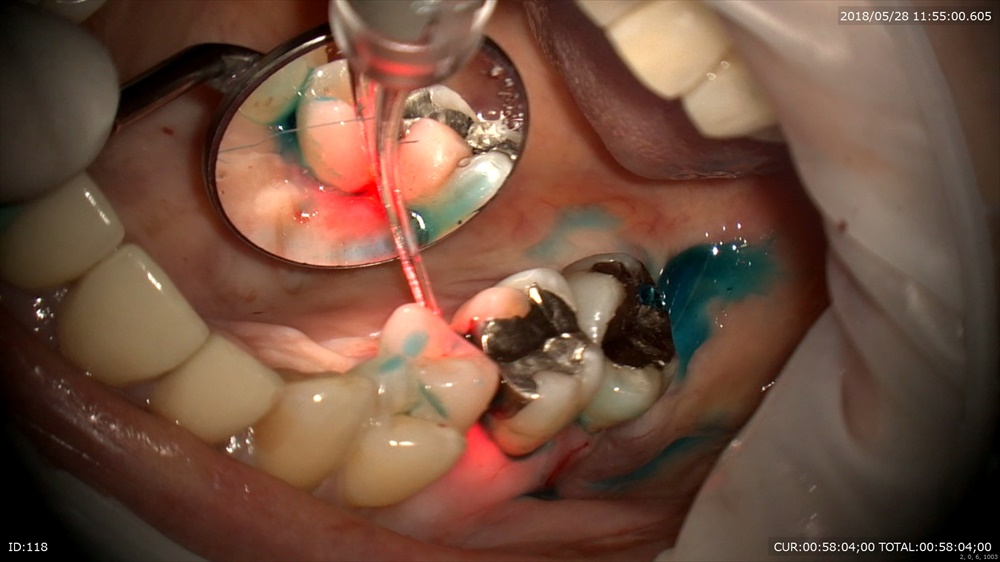

レーザー

この様にマイクロスコープで治療を行う事でまるで触られていない感覚で歯周病治療が出来ます。